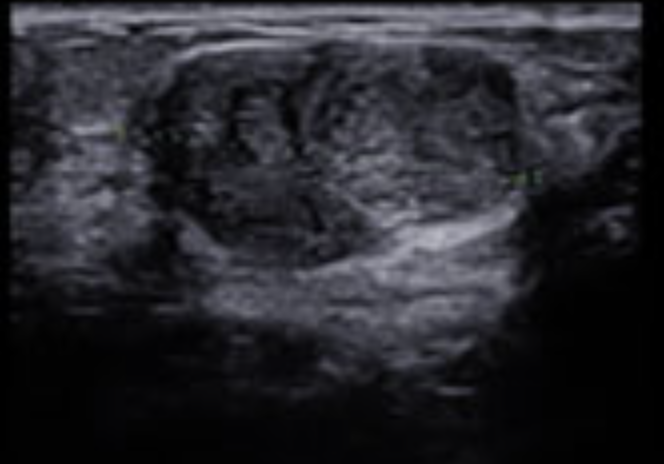

유방 섬유선종 크기, 초음파 사진

유방 섬유선종의 진단과 검사는 일반적인 진찰만으로도 진단이 가능하나 그 확률이 20~50%로 부정확할 만큼 낮아 유방 촬영, 유방 초음파를 같이 시행하여 진단합니다.

유방 섬유선종이라면 유방 촬영상 경계가 잘 보이고 둥근 결절이 보이며 내부에 석회화를 보이기도 합니다.